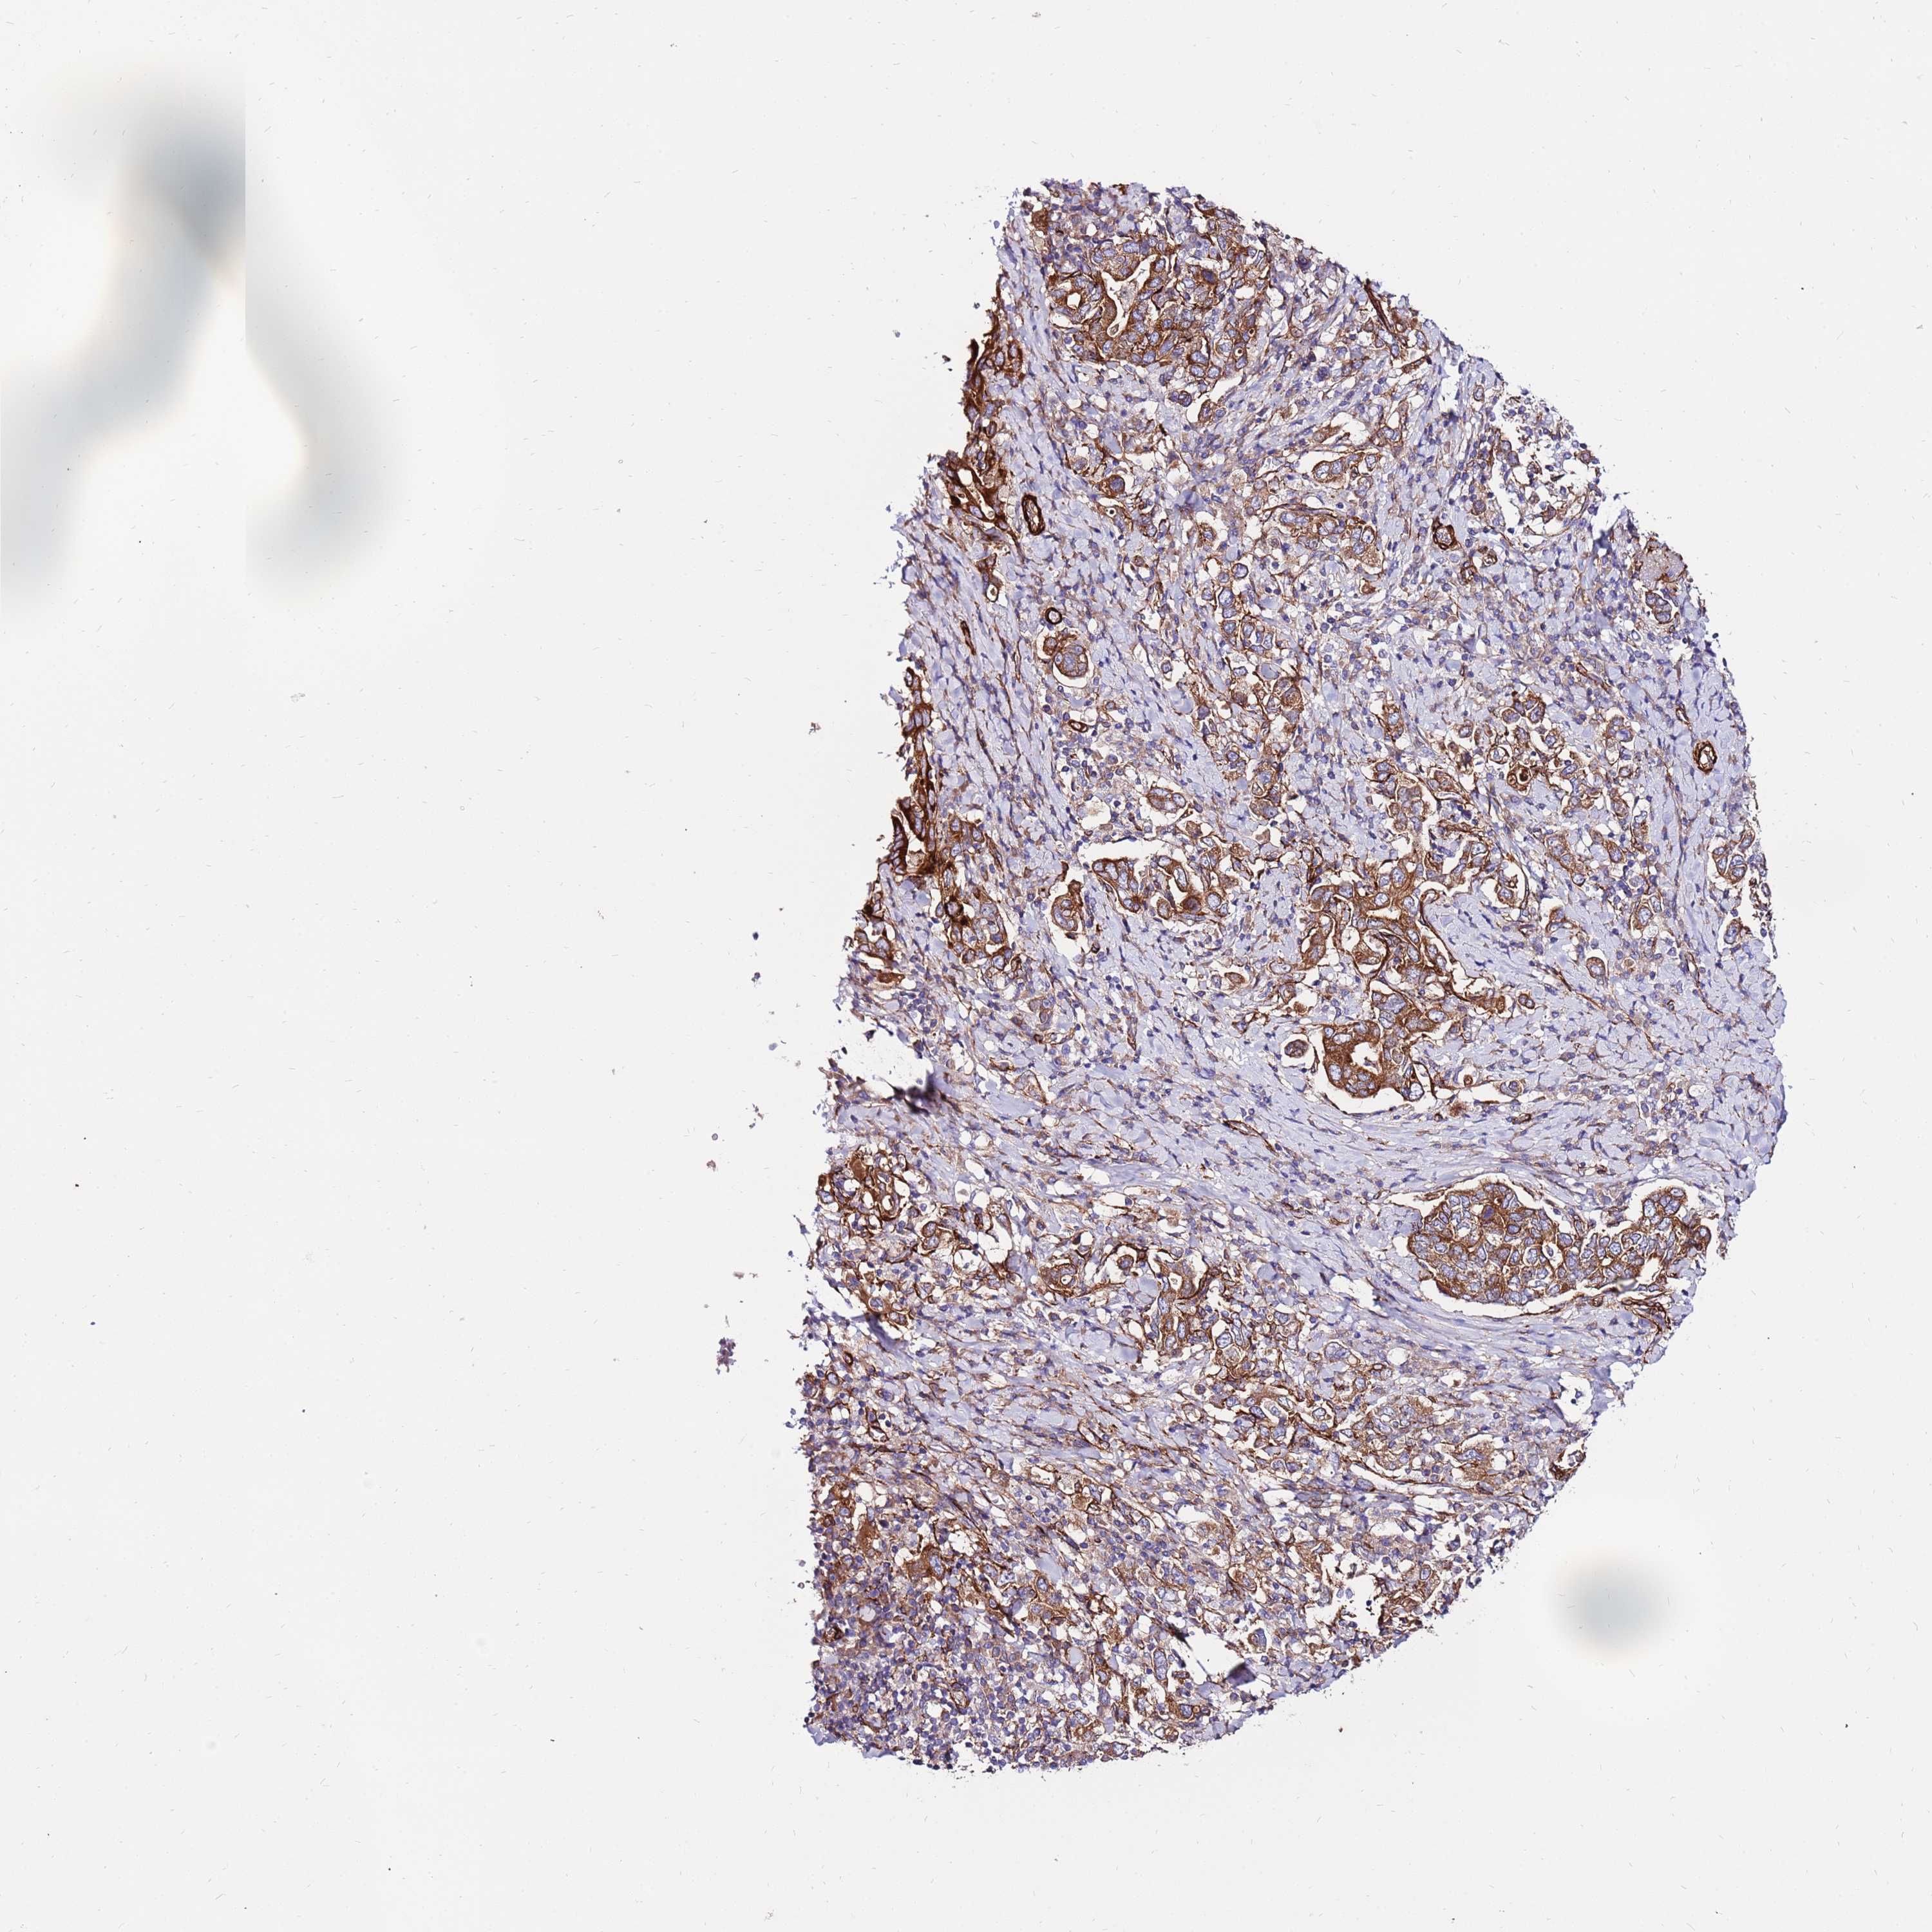

STOMACH CANCER - Protein expressioni

A mouse-over function shows sample information and annotation data. Click on an image to view it in a full screen mode. Samples can be filtered based on level of antibody staining by selecting one or several of the following categories: high, medium, low and not detected. The assay and annotation is described here.

Note that samples used for immunohistochemistry by the Human Protein Atlas do not correspond to samples in the TCGA dataset.

Antibody stainingi

Antibody staining in the annotated cell types in the current human tissue is reported as not detected, low, medium, or high, based on conventional immunohistochemistry profiling in selected tissues. This score is based on the combination of the staining intensity and fraction of stained cells.

Each image is clickable and will lead to virtual microscopy that enables deeper exploration of all samples and also displays staining intensity scores, fraction scores and subcellular localization as well as patient and tissue information for each sample.

Antibody HPA047165

Antibody HPA051029

Staining

High

Medium

Low

Not detected

Intensity

Strong

Moderate

Weak

Negative

Quantity

>75%

75%-25%

<25%

None

Location

Nuclear

Cytoplasmic/membranous

Cytoplasmic/membranous,nuclear

Adenocarcinoma, NOS